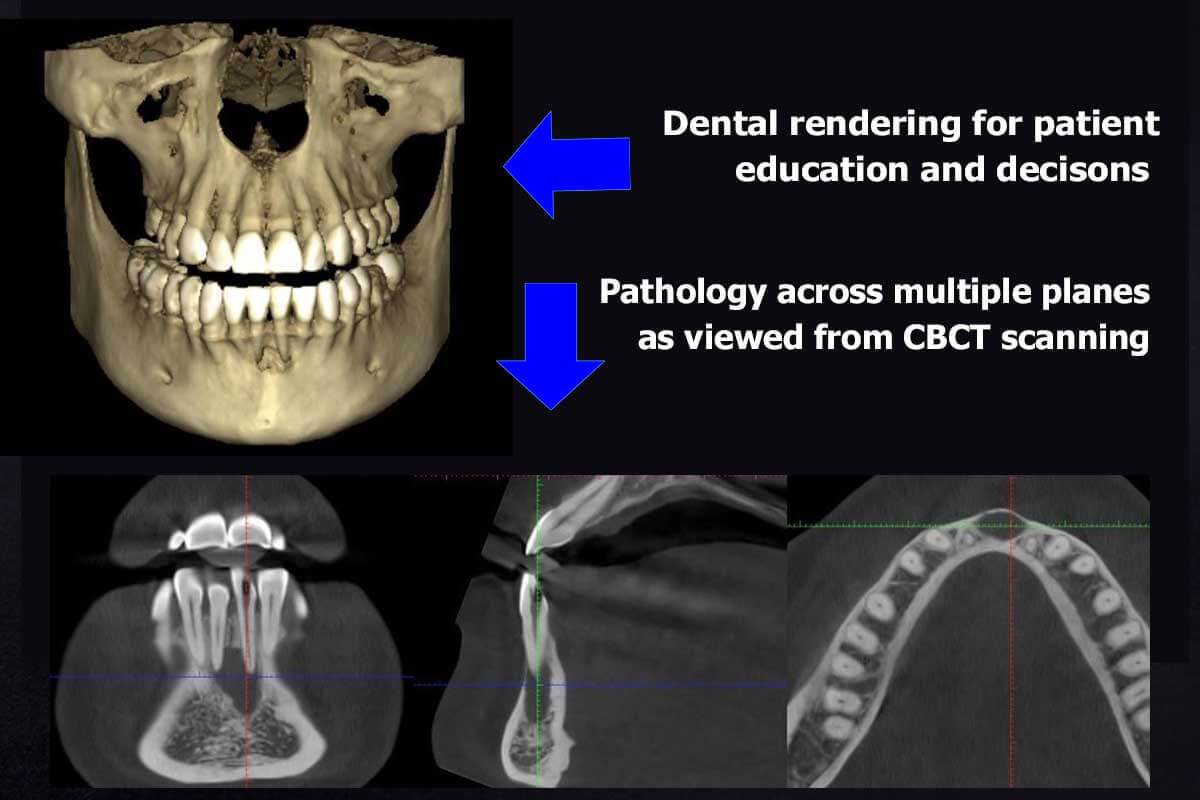

Defining “Best” in Clinical Context

“Best” is application-specific and quantifiable:

- Implant Planning: Systems with MTF >0.35 lp/mm + DLIR achieving ≤0.1mm root mean square error (RMSE) in nerve canal localization at ≤3.0 mGy

- Endodontics: Requires temporal resolution <2 sec/slice to freeze mandibular motion; systems with pulsed X-ray gating

- Orthodontics: Low-dose protocols (≤0.8 mGy) with AI-based airway segmentation (validated against spirometry)

No single system dominates all use cases. Labs must match detector specs (QDE/MTF) and reconstruction capabilities to clinical needs. Systems advertising “0.04mm resolution” without specifying dose context or MTF values are leveraging marketing semantics – physics dictates that at dental CBCT doses (<5 mGy), true resolution rarely exceeds 0.08mm.